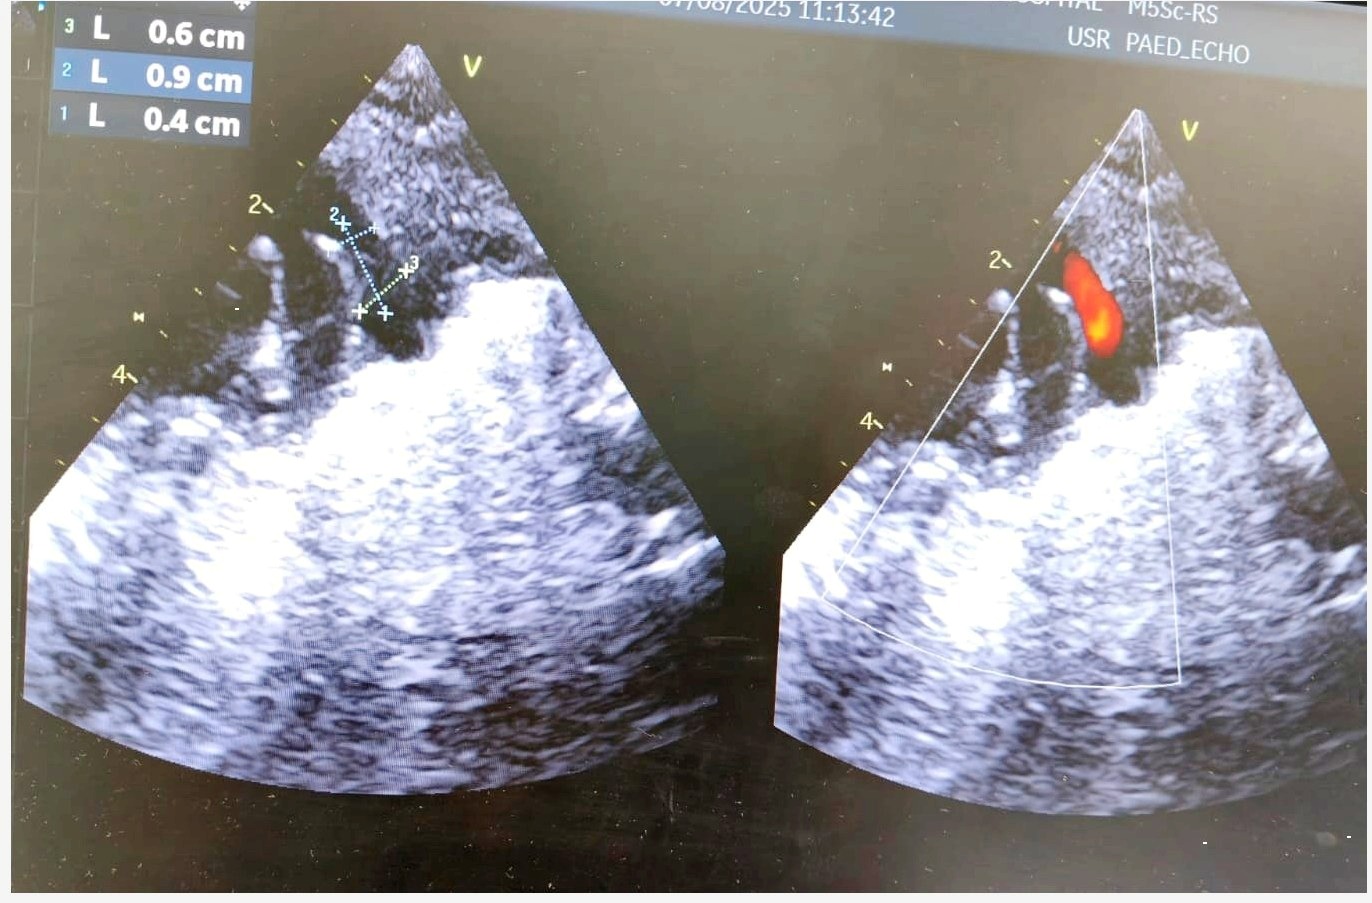

Upon admission, a chest X-ray revealed cardiomegaly and pulmonary plethora, consistent with fluid overload from left-to-right shunting. An echocardiogram confirmed the presence of a hemodynamically significant PDA, classified as Type F. The ductus arteriosus had a wide opening with specific measurements: an aortic end of 6 mm, a pulmonary artery (PA) end of 4 mm, and a length of 9 mm.

2. Procedure: A single access was obtained via the right femoral vein (RFV). A 5 x 2 mm Piccolo device was used for closure and deployed intraductally.